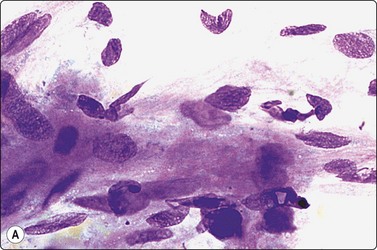

The pseudosarcomatous lesions are an important target for needling in this histogenetic group of tumors/lesions. Nodular fasciitis is among the commonest and the most frequently needled. Dahl and Åkerman reported 13 cases with cytology 1981;12 at present, our material comprises more than 70 cases, all with remarkably similar cytomorphology. In more recent investigations of the cytological features of nodular fasciitis, the results are similar to those of Åkerman and Dahl.13,14 The most important feature is the pleomorphism of the proliferating fibroblasts/myofibroblasts. Nuclei are predominantly spindly, but a proportion of cells have plump, ovoid or kidney-shaped nuclei. Bi-and/or multinucleated forms are always present and, if looked for carefully, ganglion cell-like binucleate cells with triangular shape and eccentrically placed nuclei are found (Fig. 15.1). A high cell content, nuclear pleomorphism, prominent nucleoli and the presence of mitoses may suggest malignancy, but the pale, bland nuclear chromatin is a clear indication of the benign nature of the lesion (Fig. 15.2). The correct diagnosis depends on the clinical presentation and the anatomical site (a rapidly, often tender subcutaneous nodule most frequently appearing in the upper extremity, trunk, head and neck) combined with such cytologic features as a myxoid background, actively proliferating fibroblasts/myofibroblasts and the presence of inflammatory cells.

image

Fig. 15.2 Nodular fasciitis

Poorly cohesive, proliferating fibroblasts; plump, oval, irregular nuclei, small nucleoli, bland chromatin; myxoid matrix not discernible in H&E-stained wet-fixed material (H&E, HP).